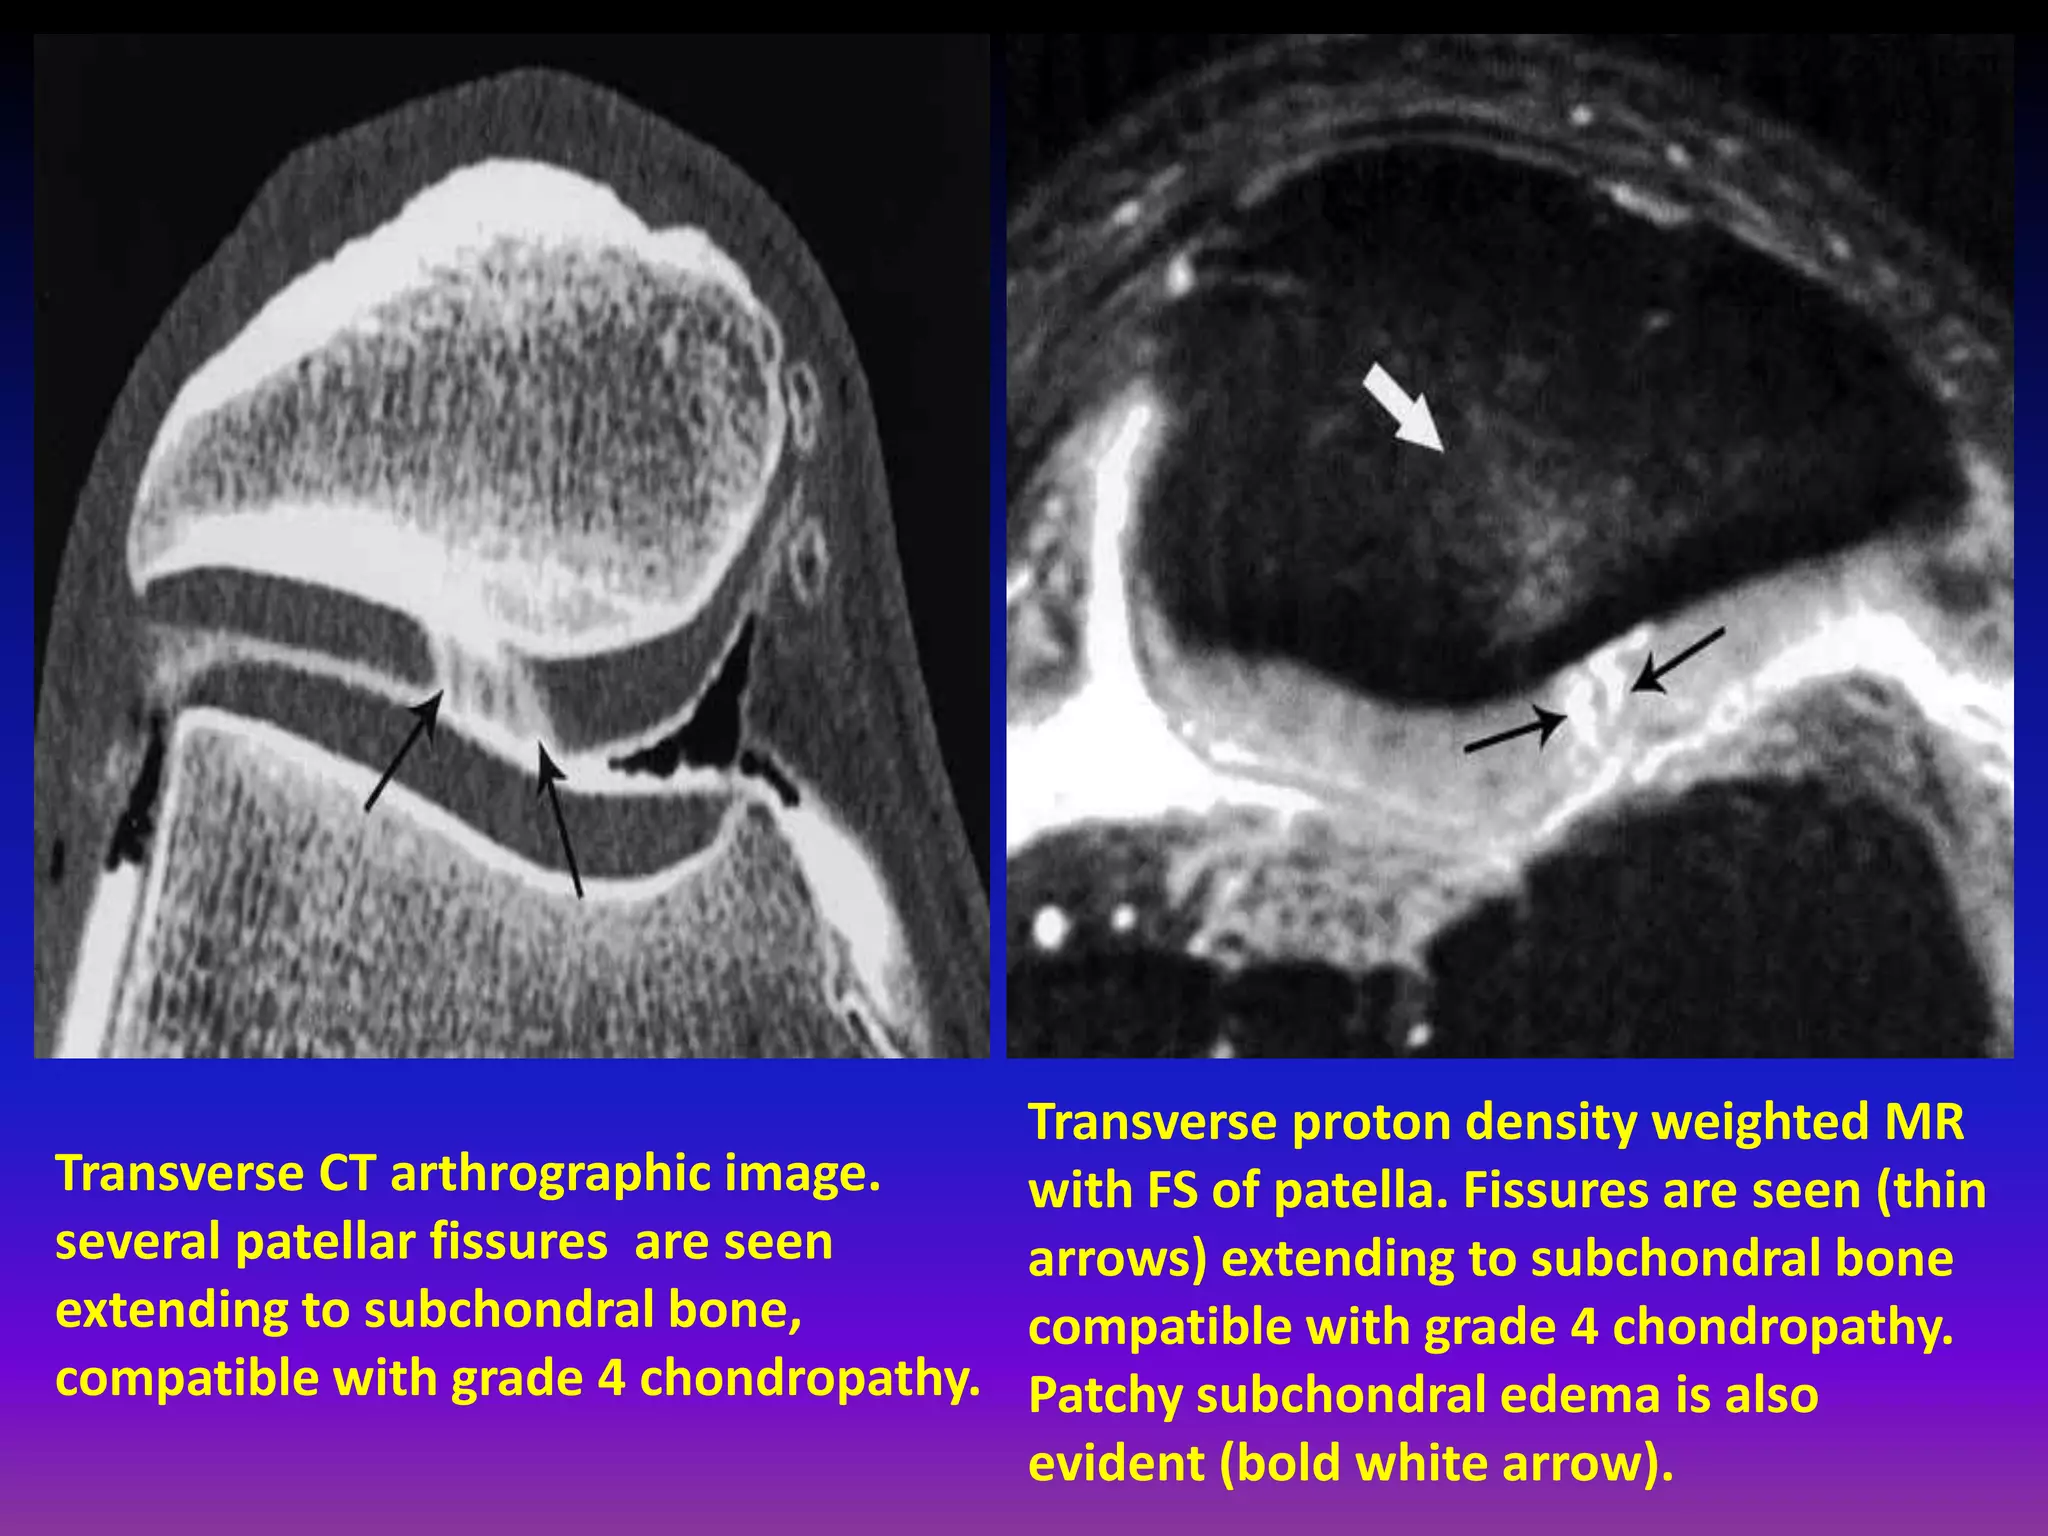

Transverse CT arthrographic image.

several patellar fissures are seen

extending to subchondral bone,

compatible with grade 4 chondropathy.

Transverse proton density weighted MR

with FS of patella. Fissures are seen (thin

arrows) extending to subchondral bone

Patchy subchondral edema is also

evident (bold white arrow).

Full thickness chondral lesion , exposed subchondral bone.